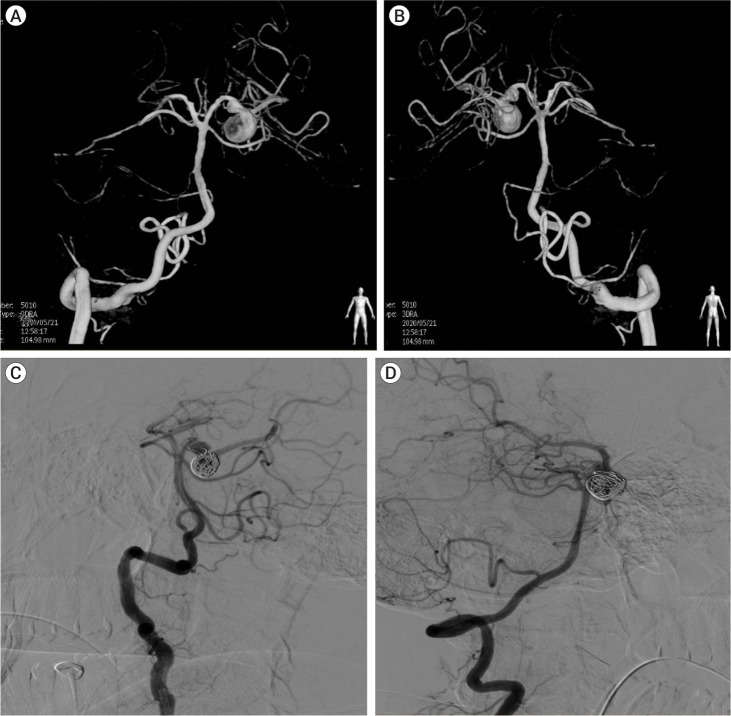

颅神经麻痹可能是颅内动脉瘤的先兆。动脉瘤血管与邻近神经之间存在典型的配对关系,从而导致颅神经病变。孤立的外展神经麻痹可能是未破裂的椎基底动脉循环动脉瘤的局部征兆。据报道,涉及小脑前下动脉(AICA)和小脑后下动脉(PICA)的动脉瘤与外展神经麻痹有关。未破裂动脉瘤的症状是由于邻近神经血管结构的肿块效应造成的。大多数外展神经麻痹在显微外科手术切除后可缓解。在此,我们介绍了一例罕见的未破裂的大脑后动脉(PCA)动脉瘤病例,该病例出现了外展神经麻痹和复视,并伴有对侧偏盲,经血管内线圈栓塞治疗后症状明显改善。

Cranial nerve palsies can be presenting signs of intracranial aneurysms. There is a classic pairing between an aneurysmal vessel and adjacent nerves leading to cranial neuropathy. Isolated abducens nerve palsy can be a localizing sign of an unruptured vertebrobasilar circulation aneurysm. Aneurysms involving Anterior Inferior Cerebellar Artery (AICA) and Posterior Inferior Cerebellar Artery (PICA) have been reported to be associated with abducens nerve palsy. The symptoms in unruptured aneurysms are due to the mass effect on adjacent neurovascular structures. Most of the abducens nerve palsy resolves following microsurgical clipping. Here, we present a rare case of an unruptured Posterior Cerebral Artery (PCA) aneurysm presenting with abducens nerve palsy and diplopia associated with contralateral hemianopsia which markedly improved following endovascular coil embolization.